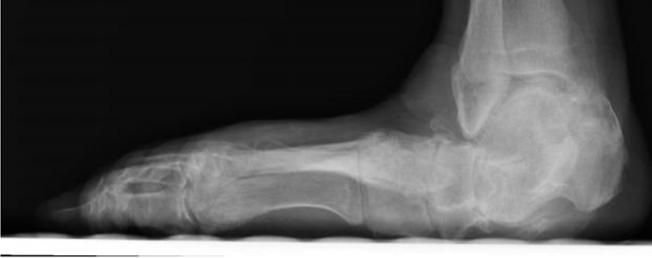

921 Charcot Neuroarthropathy of the Foot and Ankle in the Acute Setting: An Illustrative Case Report and Targeted Review

Kian Bagheri, Albert T. Anastasio, Alexandra Krez, Lauren Siewny, Samuel B. Adams

Duringthestudyperiodatotalof21participants comprising19residents(sixpostgraduateyear[PGY]1,